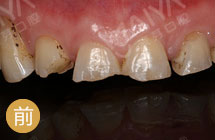

缺牙6个月,我想要回我的牙齿!

手术成功原理:针对缺牙引起牙槽骨萎缩吸收的情况,通过GPR植骨和保持位点手术形成新的牙槽骨。再通过数字化种牙完成前牙美学区的植入,实现即刻负重,拥有良好的美学效果… [详细]

前牙美学度高

植体结合稳固

术后就能吃饭

远期成功率高